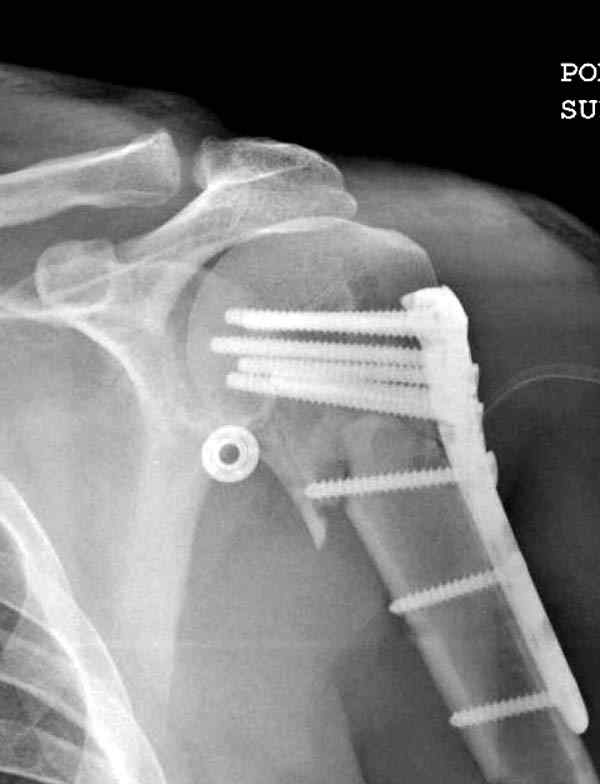

Пациентка Б.1953 г.р., врач-терапевт. Травма 27.11.08г. Падение с высоты роста. Выявлен закрытый не осложненный оскольчатый перелом хирургической шейки левого плеча со смещением. 02.12.08г. оперирована. Выполнена открытая репозиция и остеосинтез пластиной LCP Деост с дополнительной фиксацией отдельно лежащего фрагмента винтом. Послеоперационный период протекал без особенностей, заживление раны первичным натяжением. Швы сняты через 10 дней. Иммобилизация левой верхней конечности клиновидной подушкой 4 недели. По окончании срока – рентген-контроль и умеренная разработка плечевого сустава. В течении месяца функция левого плечевого сустава восстановилась удовлетворительно: поднятие руки до 110 гр., отведение - 90 гр. и до 110 гр. отведение с лопаткой. Отведение руки назад – 20 гр. Наружная и внутренняя ротация – 20 гр. Пациентка по настоянию самостоятельно вышла на работу. 27.03.09 при контрольном осмотре жалоб не предъявляет, болевой синдром в левом плечевом суставе отсутствует. Отведение плеча активно до 90 гр, пассивно с лопаткой до 110 гр., поднятие – 110 гр, отведение назад 20 гр, наружная и внутренняя ротация по 20 гр. На контрольных рентгенограммах отмечается смещение металлоконструкции, ротация головки плеча с приведением дистального отломка на 13 гр. и смещением к зади на 30 гр. Рентгенограммы прилагаются. Ваш взгляд на дальнейшую тактику лечения пациентки?

Здесь пример открытой репозиции 57 летнего с переломом плеча (1,2) смещение обнаружено на интероперационном снимке. При нормальной прямой проекция (3) угловое смещение обнаружили в аксиальной проекции (4)

После устранения смещения пластина установлена выше (5,6,7) и финальные снимки (8,9,10)

Подбор импланта тоже имеет значение, например многие импланты направлены для фиксации перелома без учета ротаторной манжетки. Предпочтительными являются низко сидящие полиаксиальные пластины, где верхние шурупы можно проводить под углом в 120 градусов. (11)

Пластина от Synthes или ее копии (надеюсь простят критику друзья из Деоста) считаются трудным из-за обширности доступа, особенно при установке верхне-заднего шурупа, где доступ надо расширять в верхнем отделе до ротаторной манжетки. Верхне сидящие импланты предназначены для проведения опоры (buttress) за бугристость плеча, но тогда приходится сталкиваться с подакромиальным импинжментом.